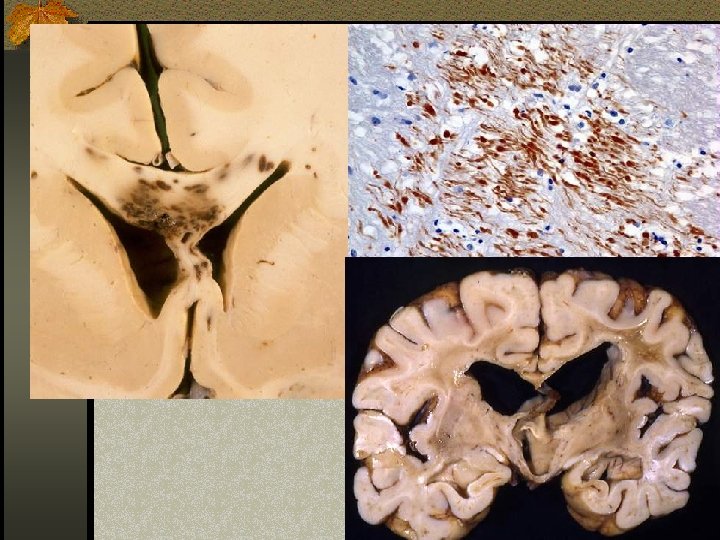

DAI n Akibat akselerasi / deselerasi terhadap white matter + hipoksia n Patients have severe LOC at impact n Grade 1: kerusakan axonal pada WM saja -67% n Grade 2: WM + corpus callosum (posterior > anterior) – 21% n Grade 3: WM + CC + brainstem

DAI n Beberapa jam : n Perdarahan dan robekan jaringan n Axonal swellings n Axonal bulbs n Beberapa hari/minggu : clusters of microglia and macrophages, astrocytosis n Beberapa bulan/tahun : Wallerian degeneration